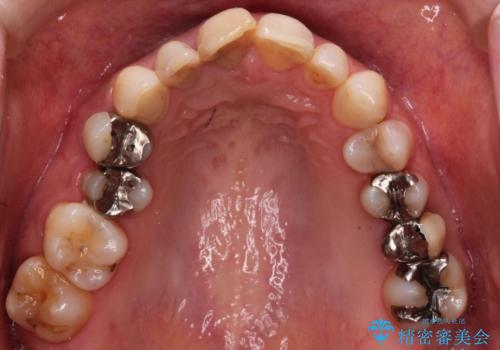

- 歯医者が怖くて悪い歯をそのままにしてしまった、悪いところを治したいとのことで来院されました。

虫歯の歯や、歯を抜いてしまったところをそのまま放置していたことにより、歯並びも悪くなっていました。

矯正をはじめ、根の治療・インプラント・セラミックによる全体治療を提案させていただき、治療をしていくこととなりました。